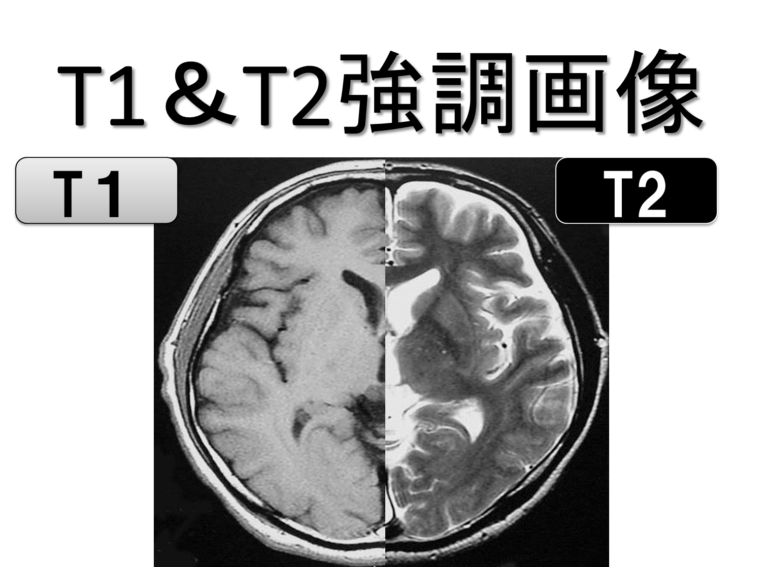

白質と灰白質はどちらもニューロンで構成されており、細胞核、有髄軸索、樹状突起が含まれています。白質は灰白質よりも多く髄鞘が形成されているため、顕微鏡や特定の画像検査で観察すると、領域の種類によって異なる外観が得られます。